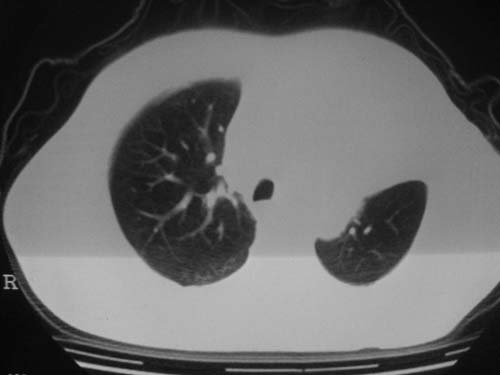

男性39岁,干咳一个月,最近胸憋气短,自己感觉发烧出汗,要求拍ct

图像质量较差请多包含,考虑肺癌,肺结核不除外,大家是否同意这种看法,请各位老师指教

左肺上叶中央型肺癌并阻塞性肺不张。

另少量心包积液。

考虑:左肺上叶中央型肺癌并阻塞性肺不张。左肺下叶囊肿或支扩。

左侧肺癌伴阻塞性肺炎,纵隔转移。

1.左侧肺癌伴阻塞性肺炎,纵隔转移。2.左下肺大泡。3.左下肺感染

纵隔淋吧结肿大

心包积液

双侧胸膜增厚

左肺上叶中央型肺癌并阻塞性肺不张,纵隔淋巴结转移。